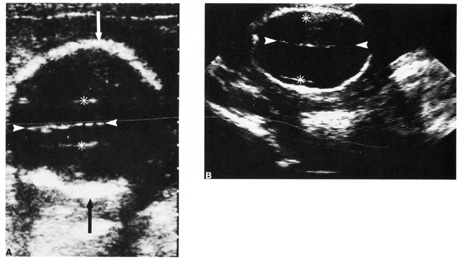

The procedure is performed under ultrasound guidance. After obtaining informed consent, an ultrasound examinations is performed to establish fetal viability, placental and fetal location, and depth to the largest pocket of amniotic fluid (Fig. 3). The maternal abdomen is prepped aseptically and a local anesthetic may be administered. A small gauge needle is then used to aspirate approximately 10 to 20 mL of amniotic fluid. The availability of the results is dependent on the amount of time needed for cell culture growth but usually is available within 7 to 10 days. The results received are a full cytogenic karyotype.

Fig. 3. A and B: Withdrawal of amniotic fluid with 20-gauge needle and 30-mL syringe.